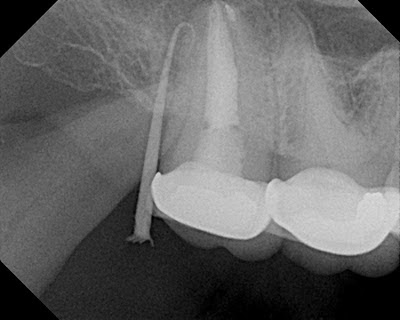

Non-surgical retx completed and symptoms persist. Discussion with patient of options:

Pt understood options and selected intentional replantation.

Atraumatic extraction, immediate resection.

3 month recall. Tooth asymptomatic and completely functional.